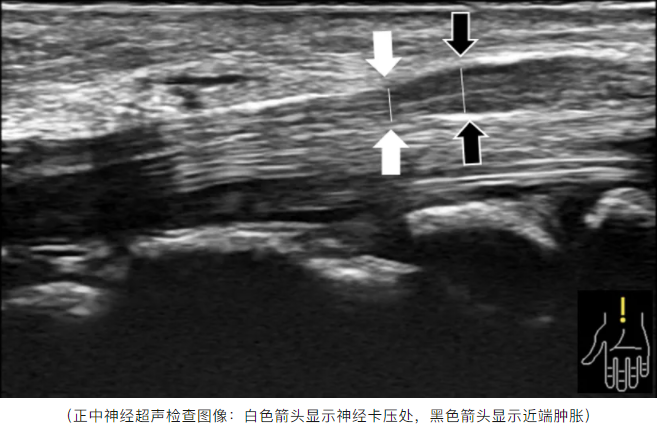

通过“右腕关节”超声检查,医生发现,张女士右手正中神经在腕横韧带处受到卡压,近端神经肿胀,确诊为腕管综合征。

肌骨超声可以观察正中神经的粗细、压迫等情况,并且确定腕部关节周围组织结构是否正常,还可以观察手或手腕在不同位置时腕管内结构的变化,普遍应用于腕管综合征及更多肌肉、骨关节相关疾病的诊断和治疗中。